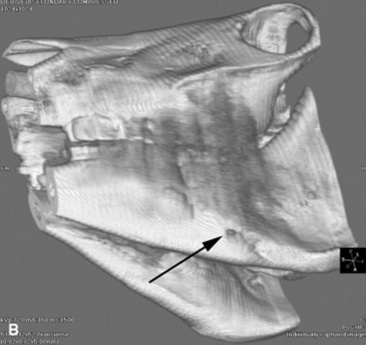

Computed tomography (CT) and magnetic resonance imaging (MRI) are of little use for evaluation of the alimentary tract (except for the head). This is mainly because of the size of the patient compared with the size of the gantry and bore in CT and MR units, respectively. Dental disorders such as abscesses and fractures can be clearly seen on CT images, especially after three-dimensional reconstructions (Fig. 32-10), and CT is also useful to detect pharyngeal and esophageal masses that may not be fully identified with conventional radiographs. CT and MRI can be used in foals that are able to be placed within the gantry or bore of the magnet; however, because of the motion of the gastrointestinal tract and the long acquisition times used with respiratory gating sequences, MRI has not been used widely to evaluate the thorax or abdomen. A single case report has been published that described the use of contrast esophagraphy and CT to aid in the surgical planning of a persistent right fourth and left sixth aortic arch that caused a vascular ring anomaly in a foal.17 However, the applications for these technologies have yet to be realized.

image image

Fig. 32-10 These are transverse (A) and three-dimensional reconstructed computed tomography images (B) of the head of a 4-year-old pony mare with chronic draining tracts from the mandible. The arrows illustrate the tract through the mandible that communicates with the apical portion of the left mandibular first molar (tooth #309).